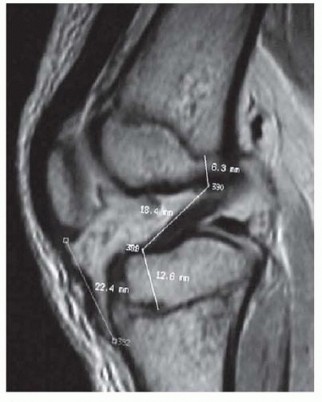

Radiographic Evaluation

Radiographs are essential to identify transverse bones, delta phalanges, and carpal coalitions (which become apparent in older children). Goldfarb et al. introduced the measurement of metacarpal and phalangeal divergence angles to assist in preoperative planning and to objectively assess postoperative reconstruction success.